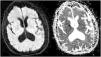

Se realizó estudio de neuroimagen control a la semana de hospitalización, apreciándose hipodensidad a nivel talámico en la región ventromedial bilateral (fig. 1) y se amplió estudio con RMN cerebral con contraste donde se observó lesión hiperseñal en secuencia T2/FLAIR con restricción a la difusión en región bitalámica ventromedial y mesencefálica rostral (fig. 2).